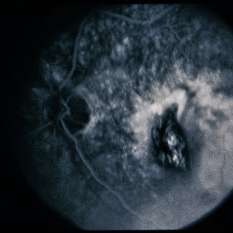

RPE Tear

RPE Tear

Sep 9 2014 by David Callanan, MD

78-year-old male, RPE tear.

Condition/keywords: retinal pigment epithelium